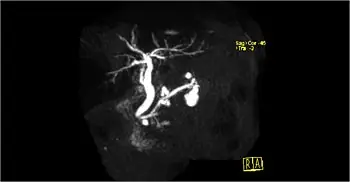

COLANGIOPANCREATOGRAFÍA POR RESONANCIA MAGNÉTICA (MRCP, POR SUS SIGLAS EN INGLÉS)

La colangiopancreatografía por resonancia magnética (MRCP, por sus siglas en inglés) es un tipo especial de resonancia magnética. Usa un programa de computadora que toma imágenes específicamente de los conductos biliar y pancreático, lugares en los que a menudo se encuentran los tumores. El líquido presente en forma natural en los conductos sirve como medio de contraste. La MRCP produce imágenes similares a una colangiopancreatografía retrógrada endoscópica (ERCP, por sus siglas en inglés) y es una excelente herramienta para visualizar los bloqueos en los conductos y los quistes pancreáticos.

La MRCP proporciona imágenes similares a una ERCP, pero sin los riesgos de un procedimiento de ERCP agresivo. La MRCP se puede usar en lugar de la ERCP con fines de diagnóstico si no se requieren intervenciones terapéuticas, como la colocación de una endoprótesis para aliviar la ictericia.

La MRCP se puede usar para diagnosticar una causa alternativa de la ictericia o una función hepática elevada, como los cálculos del conducto biliar, los tumores en el intestino delgado cerca de la abertura de los conductos biliar y pancreático o un tipo de tumor llamado neoplasia papilar mucinoso intraductal (IPMN).